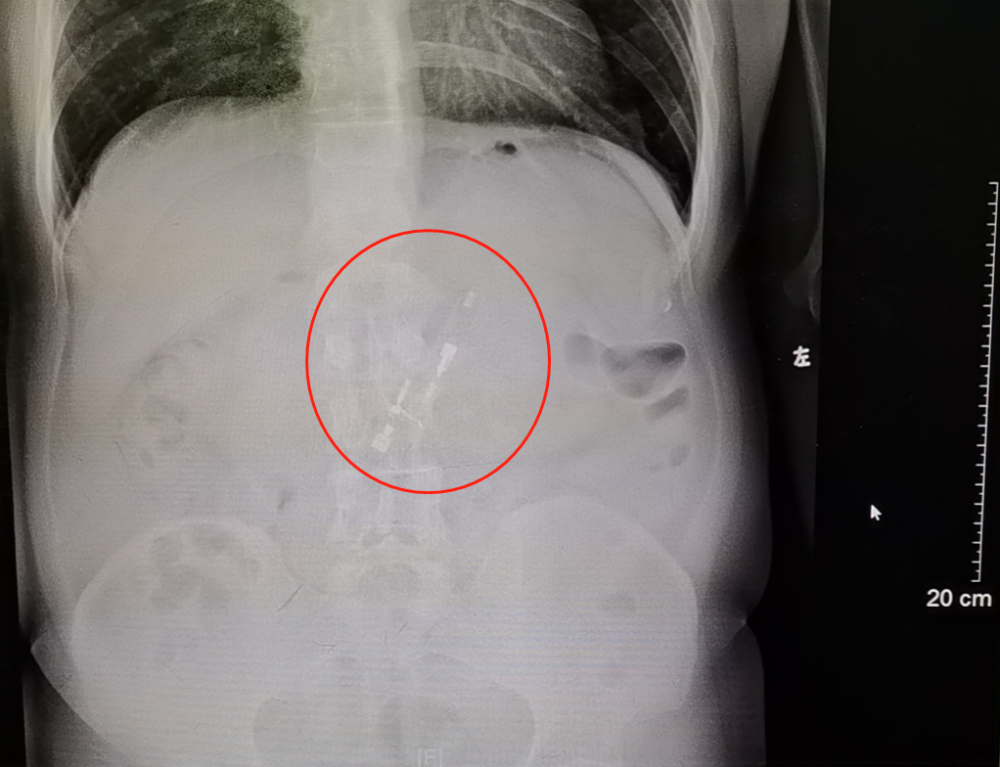

陈叔的X光片显示,他的胃里有个白色条形物质――正是他数天前吞下的打火机!他这才紧张起来,连忙到省二医消化内镜中心去做下一步的异物取出术。

X光片显示患者胃内的打火机